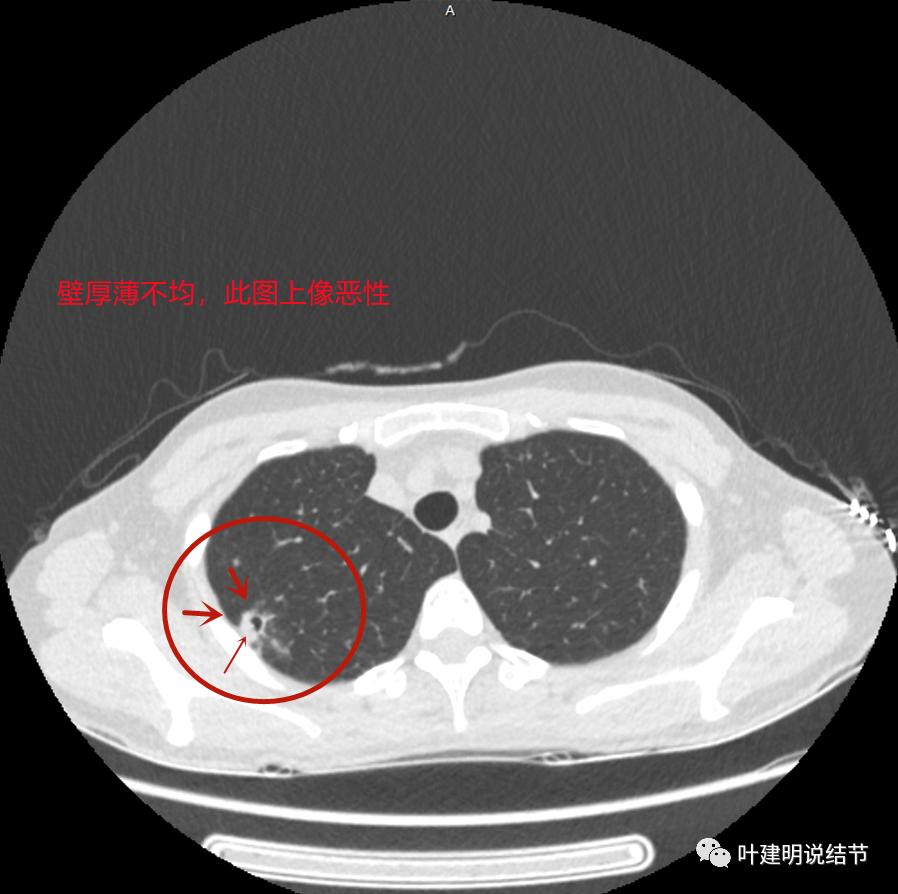

上图与恶性较为符合,空洞性病灶,壁厚薄不均,增厚部分还凹凸不平(细红色箭头所指)

上图也像恶性,但整个囊壁的密度感觉过高了点,边缘磨玻璃淡、散且模糊,邻近胸膜有增厚

再看影像印象:病灶较1年前有所进展,部分层面像恶性,囊壁厚薄不均,内面有小突起。但邻近胸膜增厚,旁边的磨玻璃部分散且淡,边界不清,实性部分边相对较光,囊壁有点状过高密度。良性可能性大些,恶性不能除外。